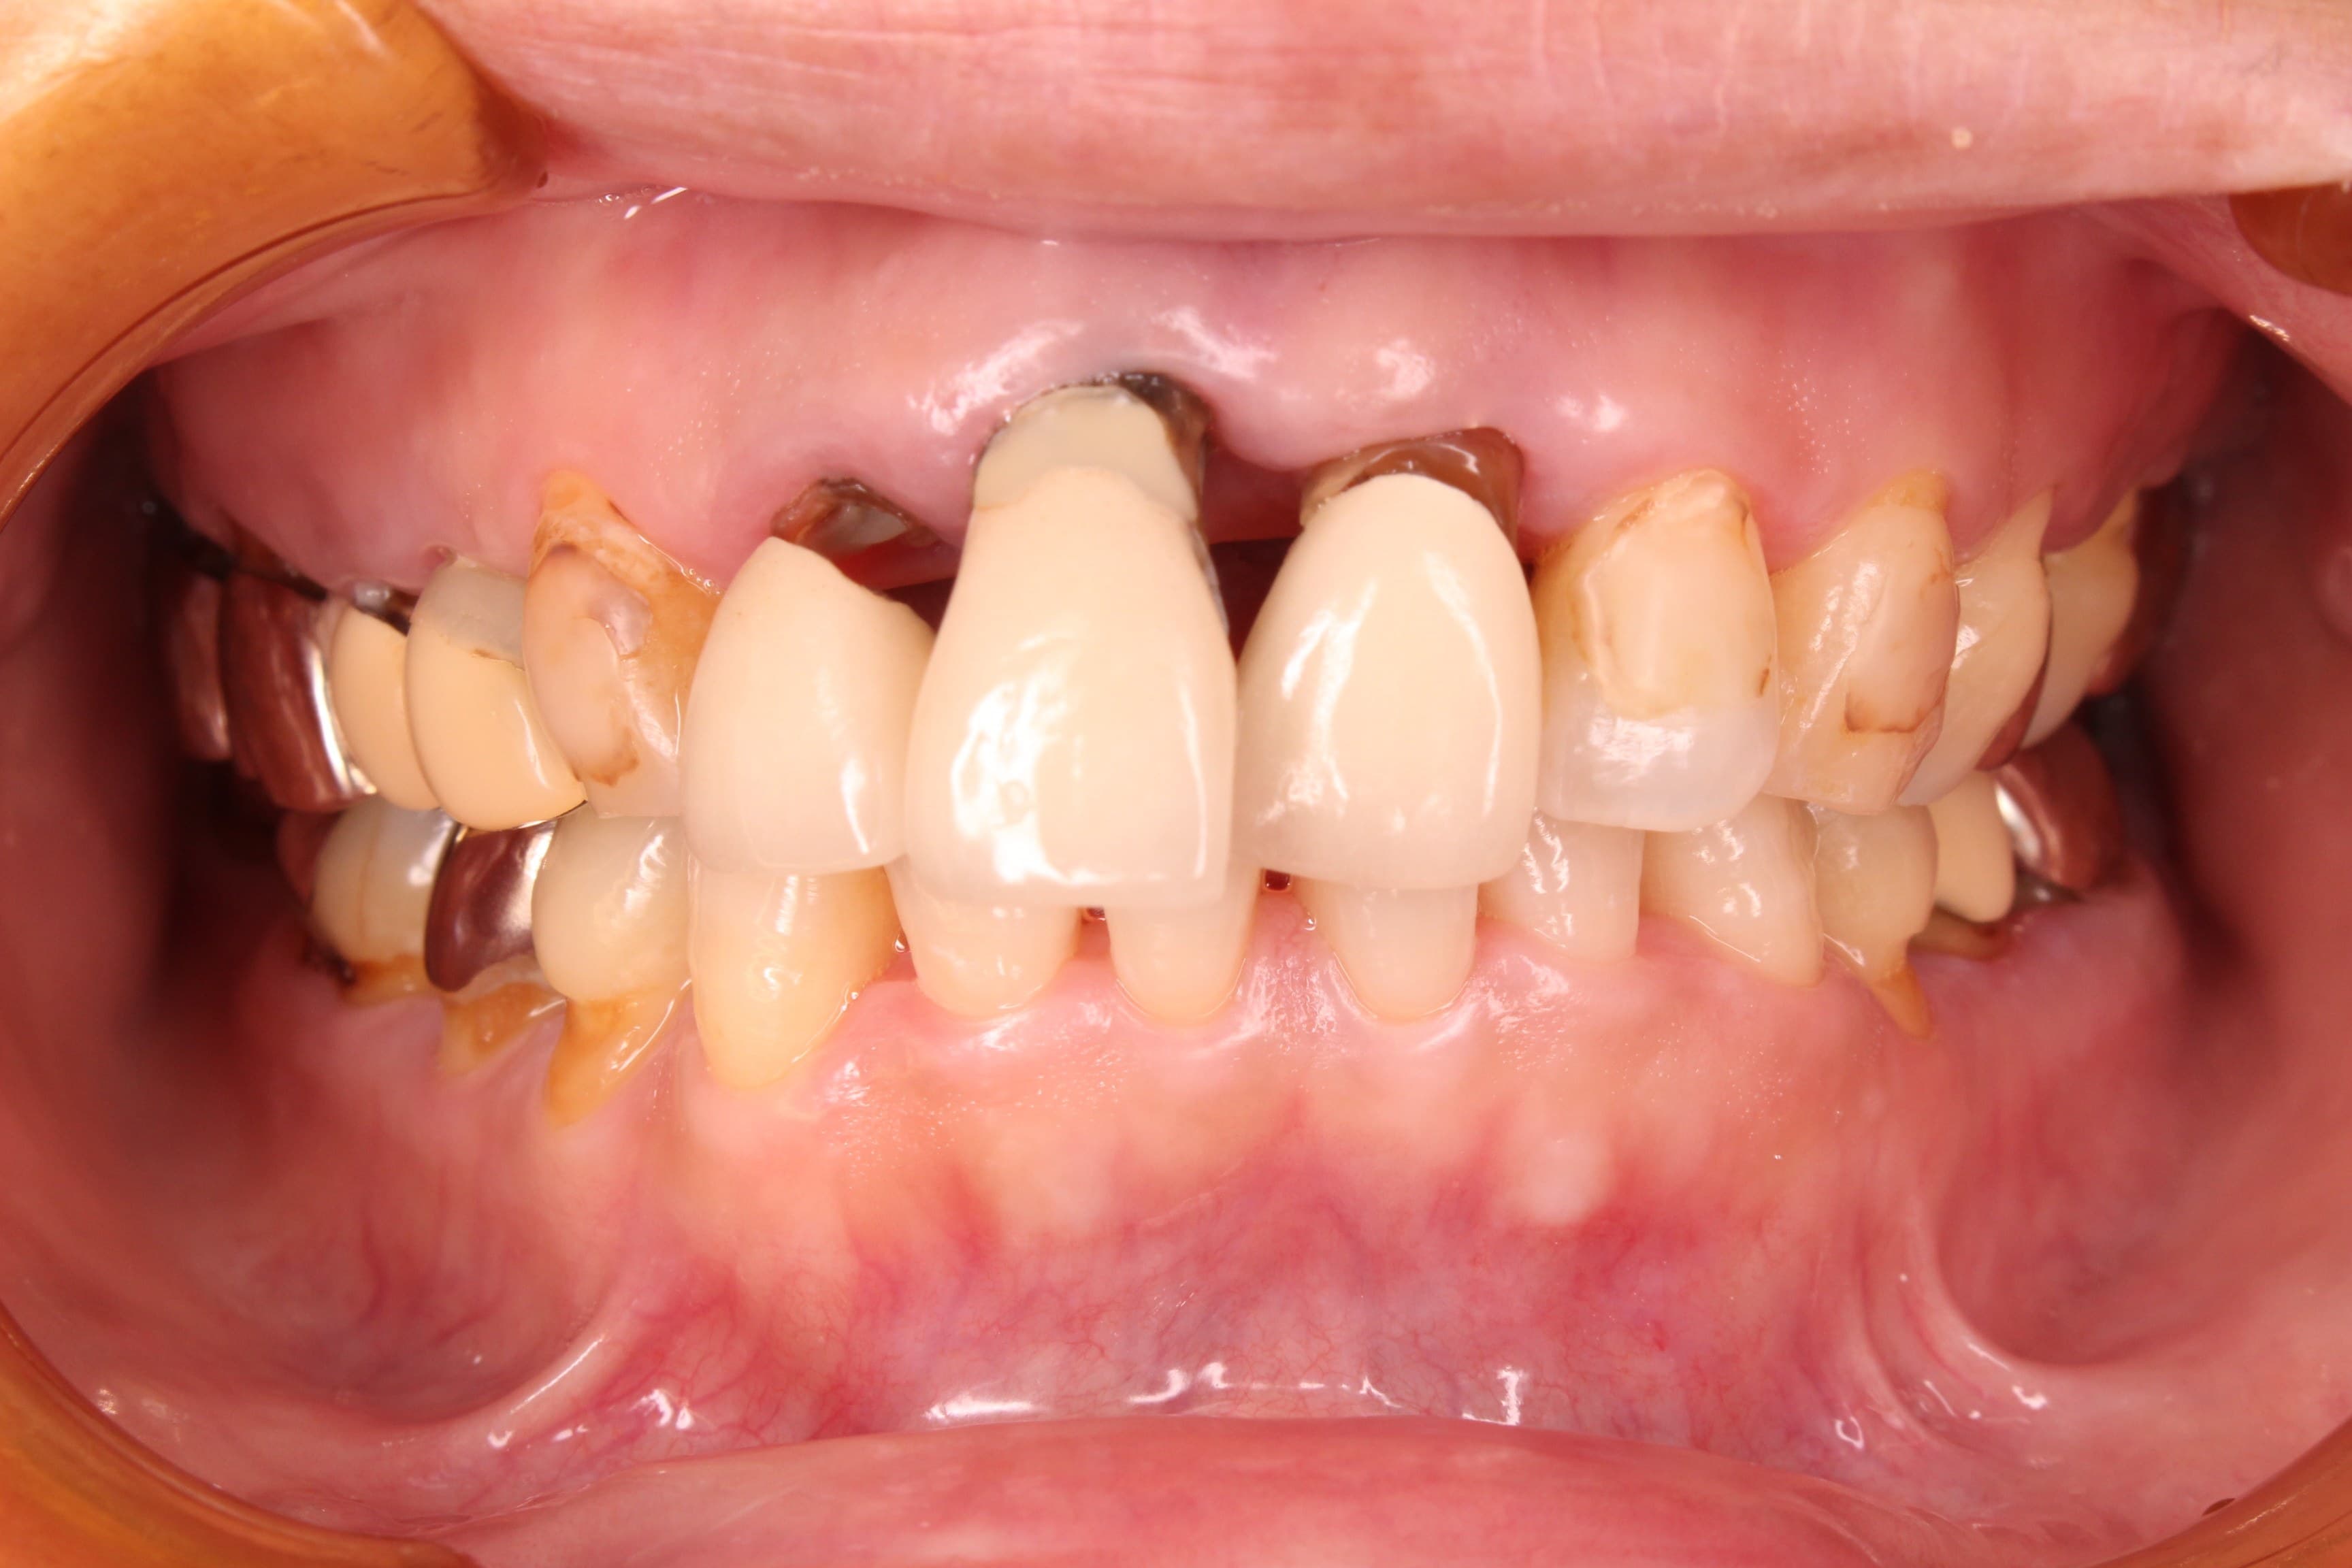

今回ご紹介する歯周専門治療のケースは、50代女性の方です。

虫歯の治療を希望されて来院されました。

口腔内の状態は、虫歯も大きく進行し、歯周病のコントロールもされておらず、出血やプラーク、歯石等の感染物質も大量に付着していた為、虫歯の治療ができる状態ではありませんでした。

虫歯の治療はこれからですが、ブラッシングの精度もかなり高くなり、虫歯や歯周病に対する予防の知識もしっかりと習得して頂く事ができました。

歯周専門治療で得た専門知識や最新の情報は、将来治療を繰り返さない為の大きな武器となります。